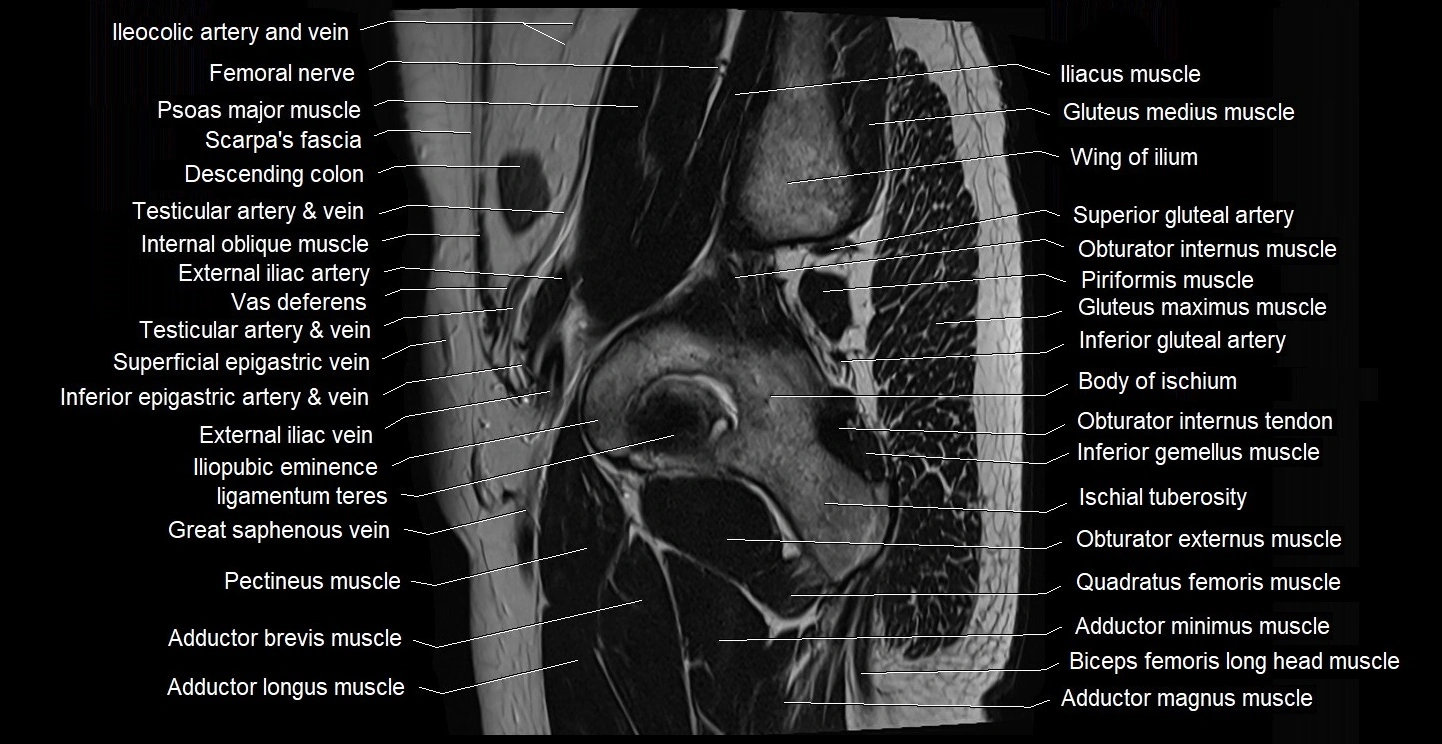

- Adductor brevis muscle

- Adductor longus muscle

- Adductor magnus muscle

- Adductor minimus muscle

- Body of ischium

- Femoral nerve

- Gracilis muscle

- Head of femur

- Iliopubic eminence

- Inferior gemellus muscle

- Inferior gluteal artery

- Ischial tuberosity

- Ligamentum teres (ligament of the head of femur)

- Obturator externus muscle

- Obturator internus muscle

- Obturator internus tendon

- Pectineus muscle

- Piriformis muscle

- Psoas major muscle

- Quadratus femoris muscle